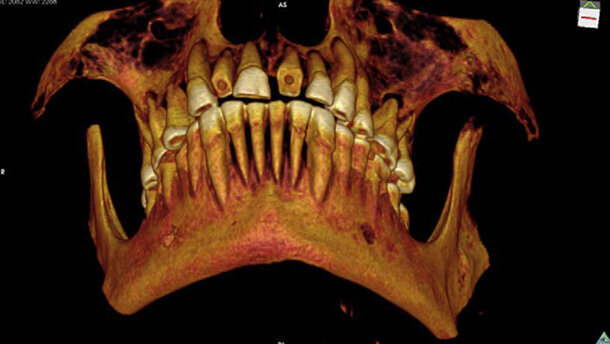

MONTREAL, CANADA - Een tweeduizend jaar geleden gemummificeerde man is waarschijnlijk overleden aan een sinusinfectie als gevolg van meerdere caviteiten en andere gebitsaandoeningen. Dat concluderen onderzoekers aan de hand van recent gepubliceerde CT-scans in een artikel in International Journal of Paleopathology.

De scans maken het mogelijk om de laatste levensdagen van de man in detail te reconstrueren. De man was tussen de 20 en 35 jaar oud en zijn gebit was in deplorabele staat. Hij had meerdere abcessen en caviteiten. Volgens de onderzoekers moet de man aan ondraaglijke pijnen hebben geleden en heeft hij daarom een bezoek gebracht aan een tandarts. Erg opmerkelijk is dat niet: tandheelkunde was bij de oude Egyptenaren een ingeburgerd fenomeen. Bovendien is het grof gemalen graan dat zij regelmatig aten slecht voor het gebit.

Zelfs een hedendaagse tandarts zou een zware kluif hebben gehad aan het behandelen van een gebit in deze toestand. Het is daarom voor te stellen dat de specialist destijds met de handen in het haar stond. Met een stuk linnen dat doordrenkt werd in een medicijn als vijgensap of cederolie heeft de tandarts destijds geprobeerd om de ernstigste caviteit op te vullen. Deze bevond zich in de linkerzijde van de kaak, tussen de eerste en tweede molaar. Het linnen zorgde ervoor dat er geen etensresten in de caviteit terecht konden komen, terwijl de medicijnen de pijn moesten verlichten.

Ondanks deze wellicht succesvolle behandeling stierf de man hooguit enkele weken erna. De exacte doodsoorzaak is onduidelijk, maar volgens de onderzoekers is het mogelijk dat een sinusinfectie de reden was. Na zijn dood werd de man gemummificeerd, waarbij de hersenen en veel organen werden verwijderd, maar het hart niet. Mogelijk duidt dit erop dat de man een bijzondere status had. De mummie werd vervolgens in een kist gelegd en begraven in Thebe. In 1859 werd de mummie ontdekt door James Ferrier en naar Montreal (Canada) gebracht, waar deze zich tot vandaag bevindt in een museum behorende bij de McGill Universiteit.

Doordat CT-scans nu in een zes keer zo hoge resolutie gemaakt kunnen worden als in de jaren negentig, kon een groep wetenschappers onder leiding van Andrew Wade de mummie nauwkeurig onderzoeken. Zij stellen in hun artikel dat hiermee voor het eerst een dergelijke vulling bij een oude Egyptenaar is aangetroffen. In tegenstelling tot de tegenwoordig gangbare dentale vullingen was deze niet bedoeld om het element te stabiliseren. “Het vullen van een grote interproximale caviteit met een waarschijnlijk in medicijnen gedrenkte linnen afdekmateriaal is een uniek voorbeeld van dentale interventie in het oude Egypte,” schrijft Wade. (bronnen: Archeologieonline.nl, LiveScience)